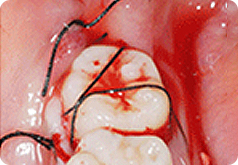

치아이식

이식한 치아 고정(4주)